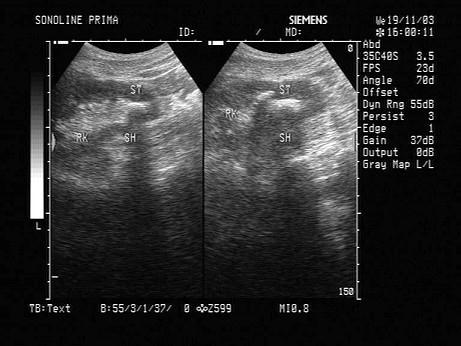

结合超声图像,该病例肾结石为哪一部位?(?)A.下极肾盏B.中极肾盏C.上极肾盏D.肾门E.肾乳头处

问题 结合超声图像,该病例肾结石为哪一部位?(?)

选项 A.下极肾盏 B.中极肾盏 C.上极肾盏 D.肾门 E.肾乳头处

答案 A